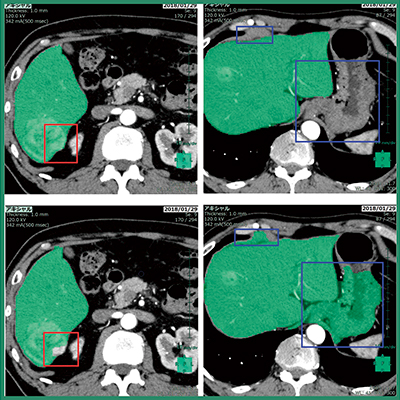

また,肝臓解析(CT)では,ディープラーニングを用いて設計した肝臓領域抽出を実装した(図3)。一般的に,ディープラーニング技術では,画像解析の分野において何を特徴とすべきかをコンピュータが自動的に学習できることが特徴であり(従来はソフトウエア開発者が画像の特徴を手動で設計),ディープラーニングが医用画像のポストプロセッシングに用いられることに対する期待は非常に高い。肝臓以外の臓器抽出エンジンにおいても,随時改良を進めていきたいと考えている。なお,VINCENTは臨床現場で学習することはない。

図3 自動抽出された肝臓領域(緑色)

赤枠,青枠は用いた手法の違いにより差異が出た領域

上段:ディープラーニングを用いて設計した肝臓領域抽出の結果画像例

下段:従来の肝臓抽出エンジンの結果画像例